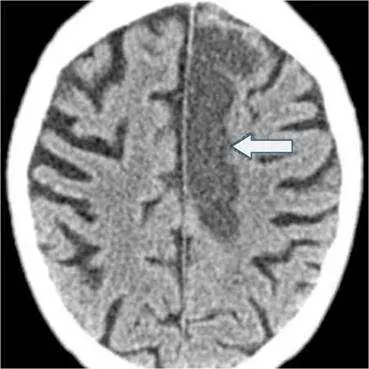

本題圖片為腦部 CT 平掃(non-contrast CT)橫切面(axial slice),影像特徵如下:

- 影像模態:頭部 CT,腦部軸切面,腦窗(brain window)設定

- 箭號所指位置:白色箭號指向左側大腦半球(left cerebral hemisphere)的一處異常區域

- 異常區域特徵:箭號指向的區域呈現明顯的低密度(hypodense)改變,與周圍正常腦組織相比顏色較深(darker area),邊界不甚清楚,範圍較大,累及皮質(cortex)及皮質下白質(subcortical white matter)

- 周圍結構:對側(右側)腦組織密度相對正常;腦室系統隱約可辨;灰白質界面(gray-white matter differentiation)在病灶側模糊

- 無高密度影:病灶區域未見高密度(hyperdense)出血訊號

此低密度區域分佈符合腦部血管